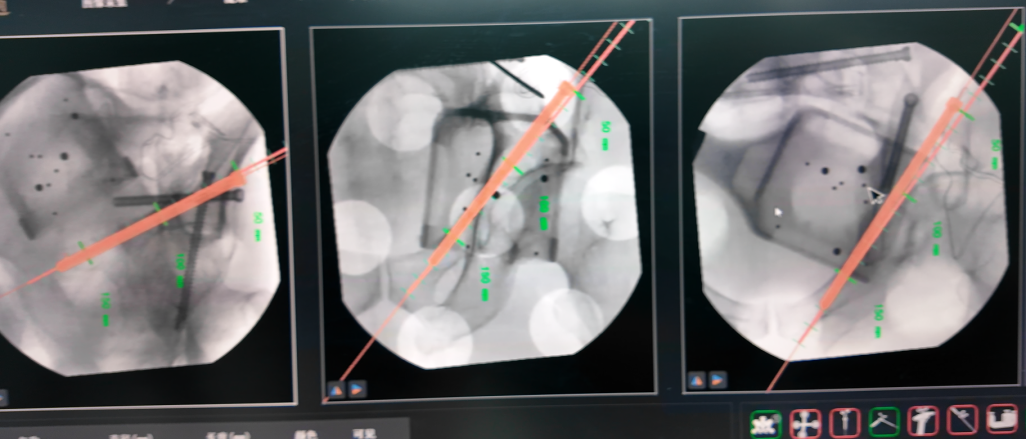

术中

机械臂按预设路径自动执行复位操作,精度高达毫米级,医生仅需通过几个微小切口置入内固定螺钉。